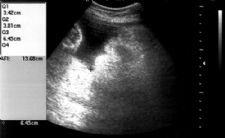

- Amniotic Fluid Index (AFI)

- Measure of vertical measurement (centimeters) of deepest fluid pocket in each of four abdominal quadrants

- Saggital plane

- Measurement line should exclude umbilical cord/fetal parts

Single Fluid Pocket >= 2 cm.

- Must be demonstrable in at least two anatomic planes